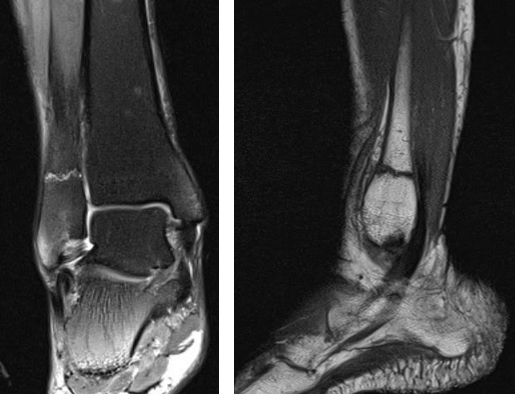

4. МРТ при переломе надколенника:

• Линия перелома: гипоинтенсивный сигнал на Т1 ВИ и Т2ВИ

• Окружающий отек костного мозга

• Разрыв суставного хряща

• Выпот в суставе

• ± разрыв медиального/латерального удерживателя/медиаль-ной бедренно-надколенниковой связки

• ± ↑ интенсивности сигнала на Т2/слабость/нарушение целостности в области сухожилия надколенника и четырехглавой мышцы

Что покажут снимки МРТ колена при переломе надколенника

- МРТ проводится, если имеются подозрения на вывих надколенника или повреждение сухожилия четырехглавой мышцы/связки надколенника

- При вывихе надколенника - ушиб вдоль нижнемедиального края надко¬ленника и переднего края латерального мыщелка бедренной кости

- Оценка внутренней поддерживающей связки надколенника (отрыв от места прикрепления к надколеннику или бедренной кости)

- Костно-хрящевые фрагменты

- Утолщение надколенника

- Разрушение надколенника

- Волнообразное изображение волокон при разрыве сухожилия четырехглавой мышцы или собственной связки надколенника.